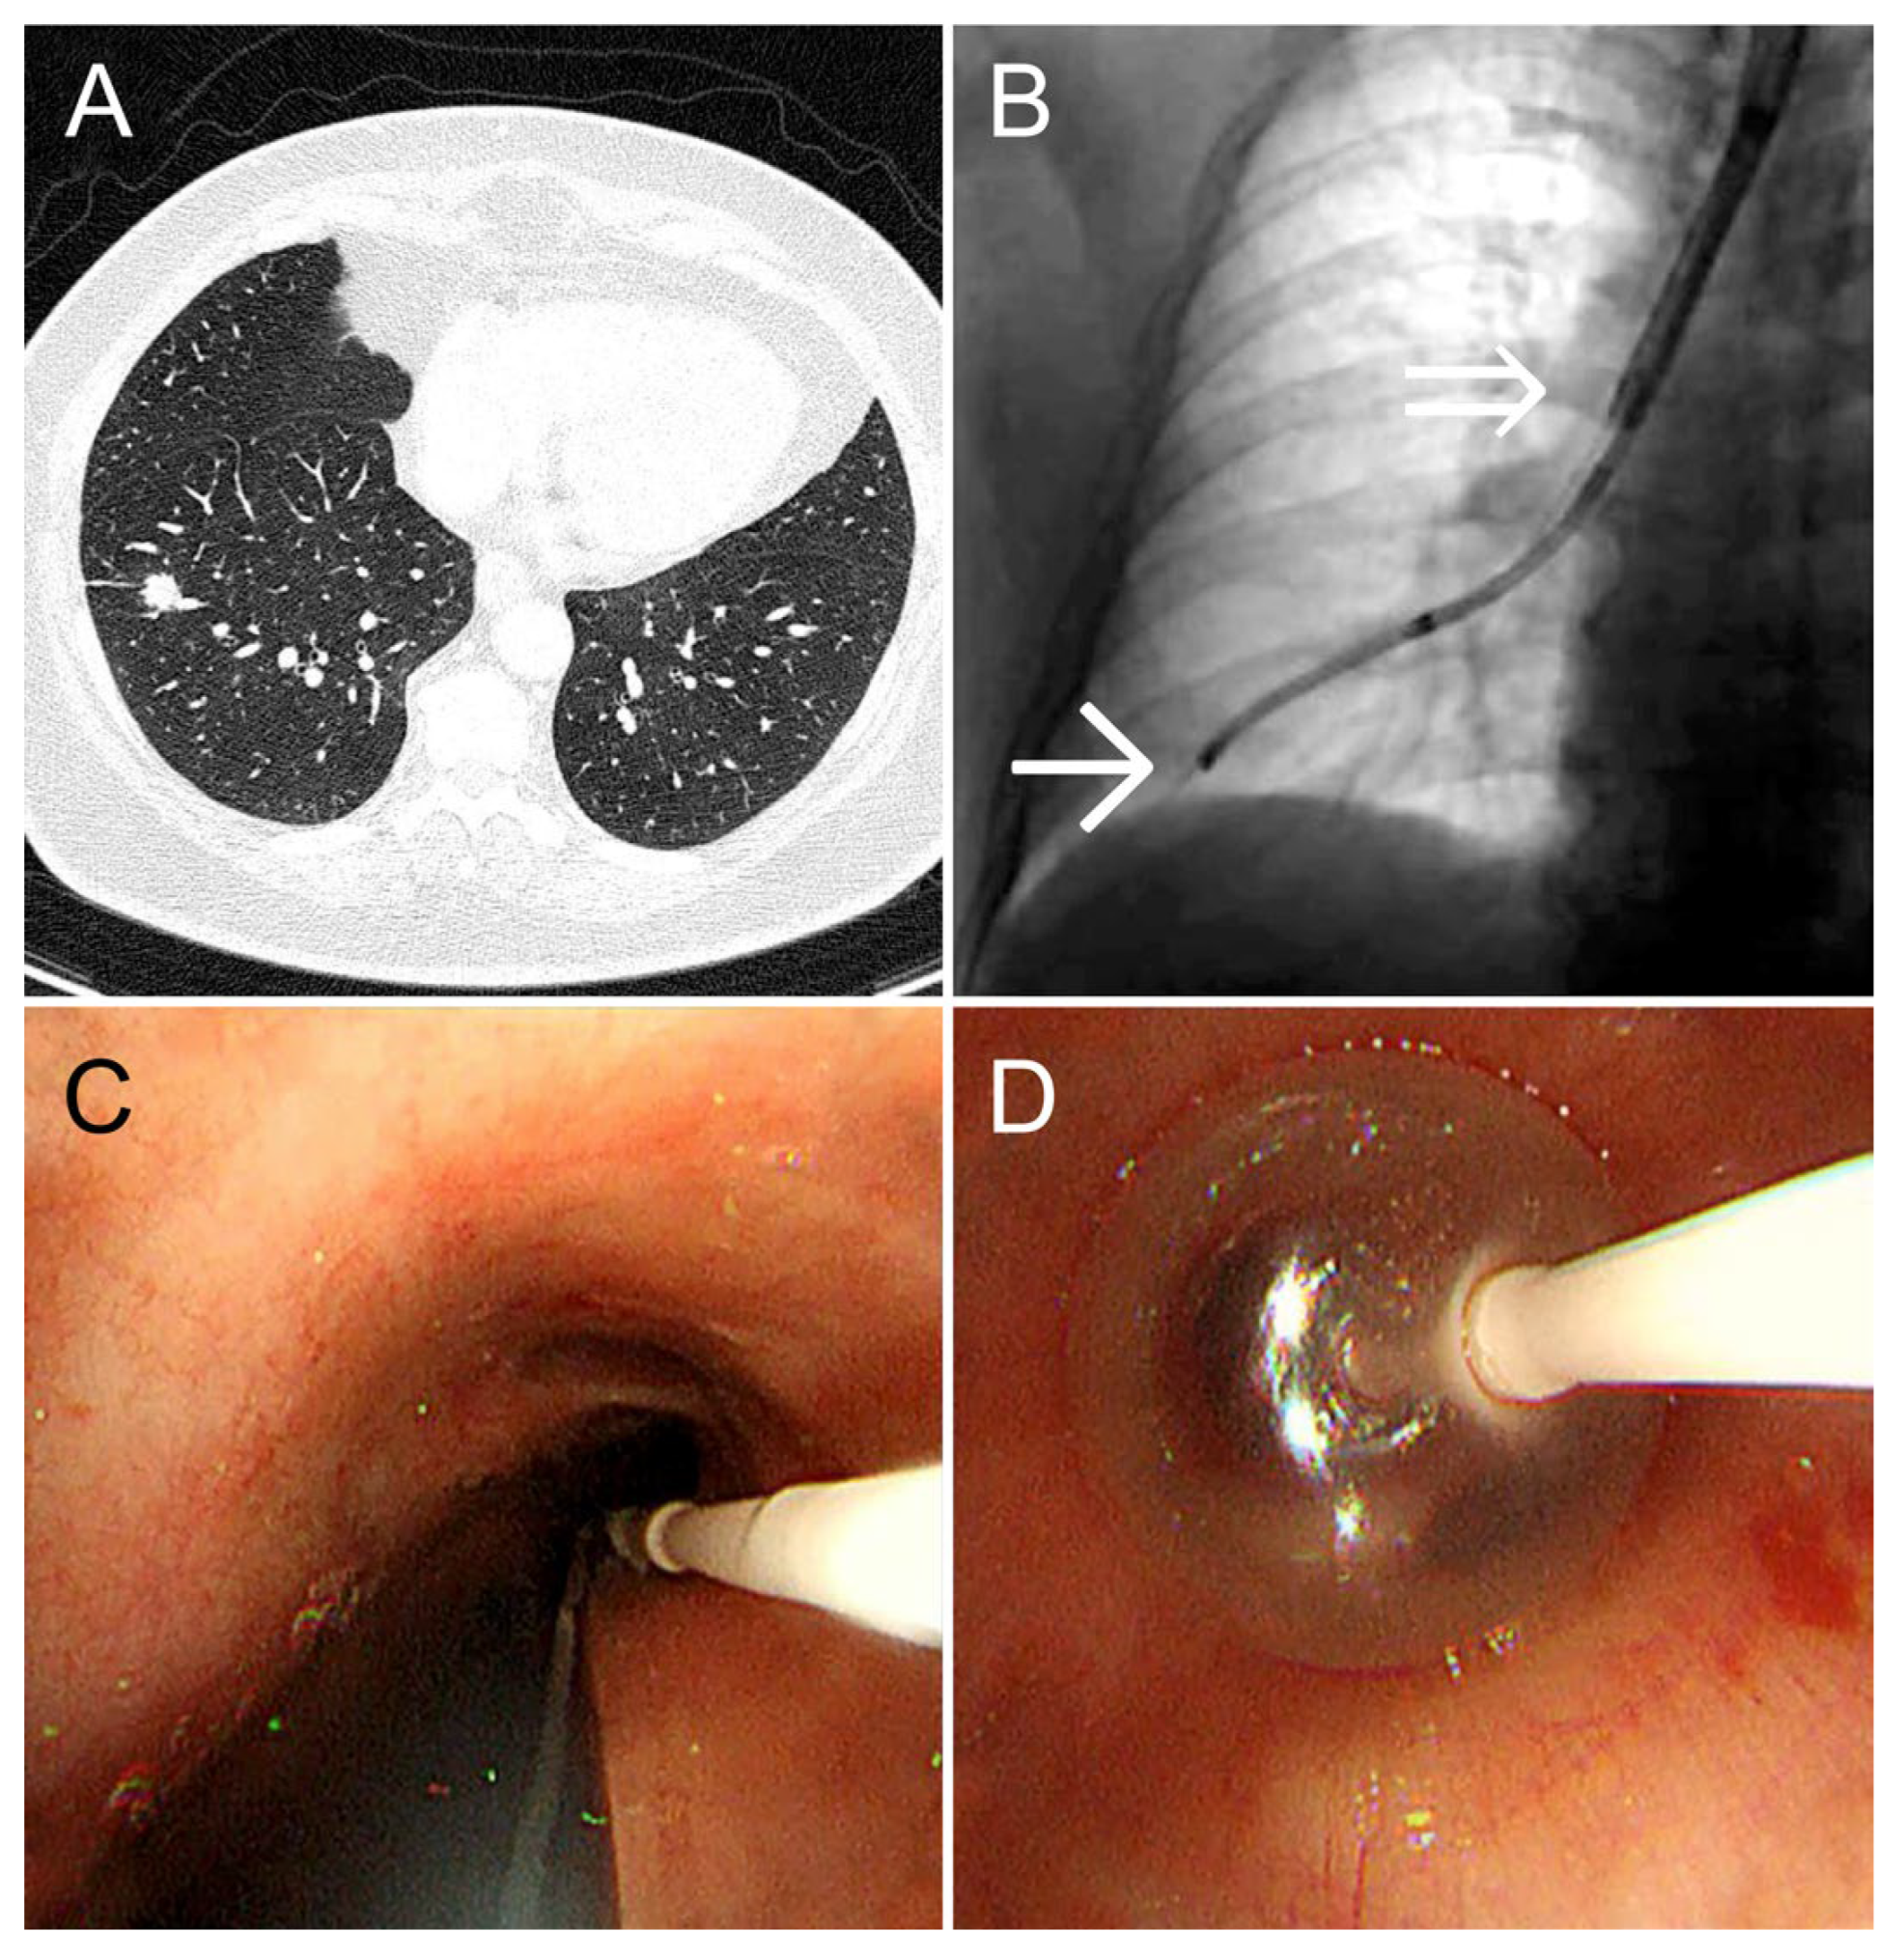

A 55-year-old woman (height: 152 cm; weight: 88 kg) with bronchial asthma and a history of treatment for peritoneal cancer underwent a follow-up CT scan for peritoneal cancer surveillance. The scan revealed a 1.2-cm solid nodule in the S8 periphery of the right lower lobe. She was referred to our department for diagnosis and treatment. Owing to her short stature and obesity, her tracheobronchial tree was relatively narrow, complicating tracheal intubation. Therefore, we selected the dual-scope method, which omits tracheal intubation. An ultrathin bronchoscope was guided to the lesion, and cryobiopsy was performed using our method, Bleeding was completely controlled by 3 min of balloon occlusion at the right basal bronchus. TBLC was performed in 31 min, maintaining SpO2 at 98–99% (Figure 3). The diagnosis was primary lung adenocarcinoma.

Figure 3. (A) A 1.2-cm solid nodule is observed in the peripheral region of the lower right lobe B8a. (B) X-ray fluoroscopy image taken during cryobiopsy. The single arrow (→) indicates the tip of the ultrathin bronchoscope, and the double arrow (⇒) indicates the tip of the therapeutic bronchoscope. (C) Bronchoscopy findings immediately before cryobiopsy. The ultrathin bronchoscope and balloon catheter are observed simultaneously. (D) After the ultrathin bronchoscope is removed, the balloon catheter is inflated under endoscopic visualization.